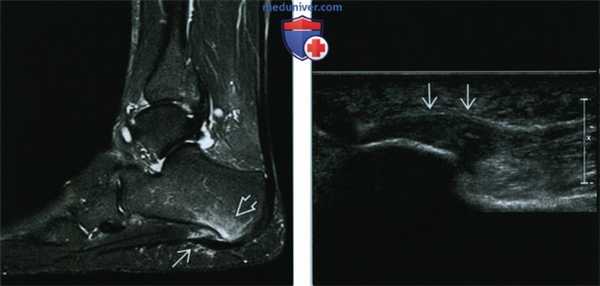

(Левый) При МРТ в сагиттальной плоскости в режиме STIR определяются утолщение фасции и отек прилежащих тканей, в том числе заднего отростка пяточной кости. Отсутствие эрозивных изменений кортикального слоя позволяет отличить фасциит от энтезопатии, вызванной спондилоартропатией.

(Правый) При УЗИ в продольной проекции визуализируется характерная картина подошвенного фасциита: утолщение фасции и гипоэхогенная структура ее центральной порции.